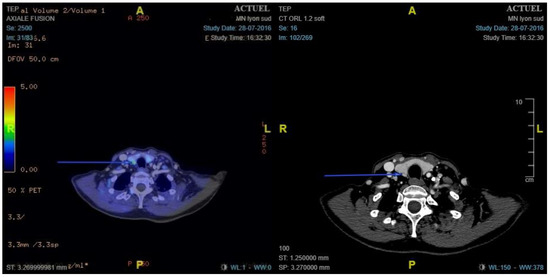

- Preoperative 18F-choline PET/ceCT data: lesion location, number of lesions, lesion size, and maximum standardised uptake value (SUVmax)